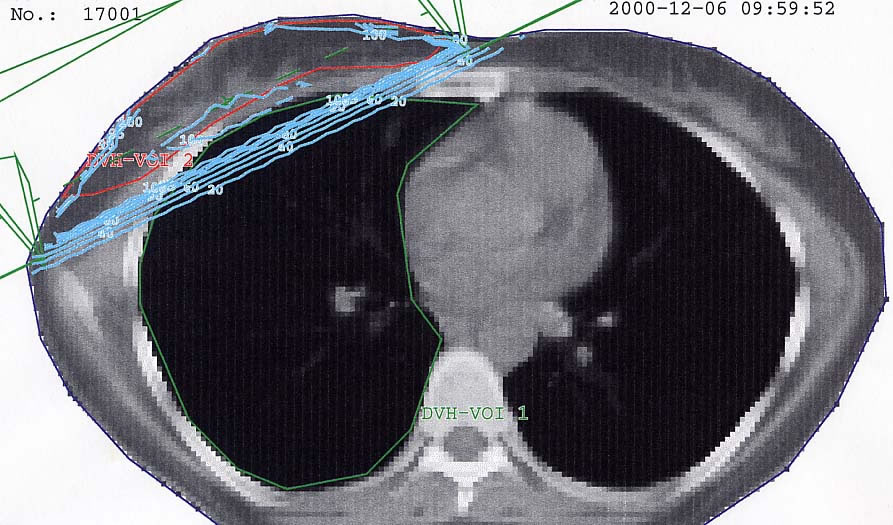

Mammakarzinom: Bestrahlungsplan